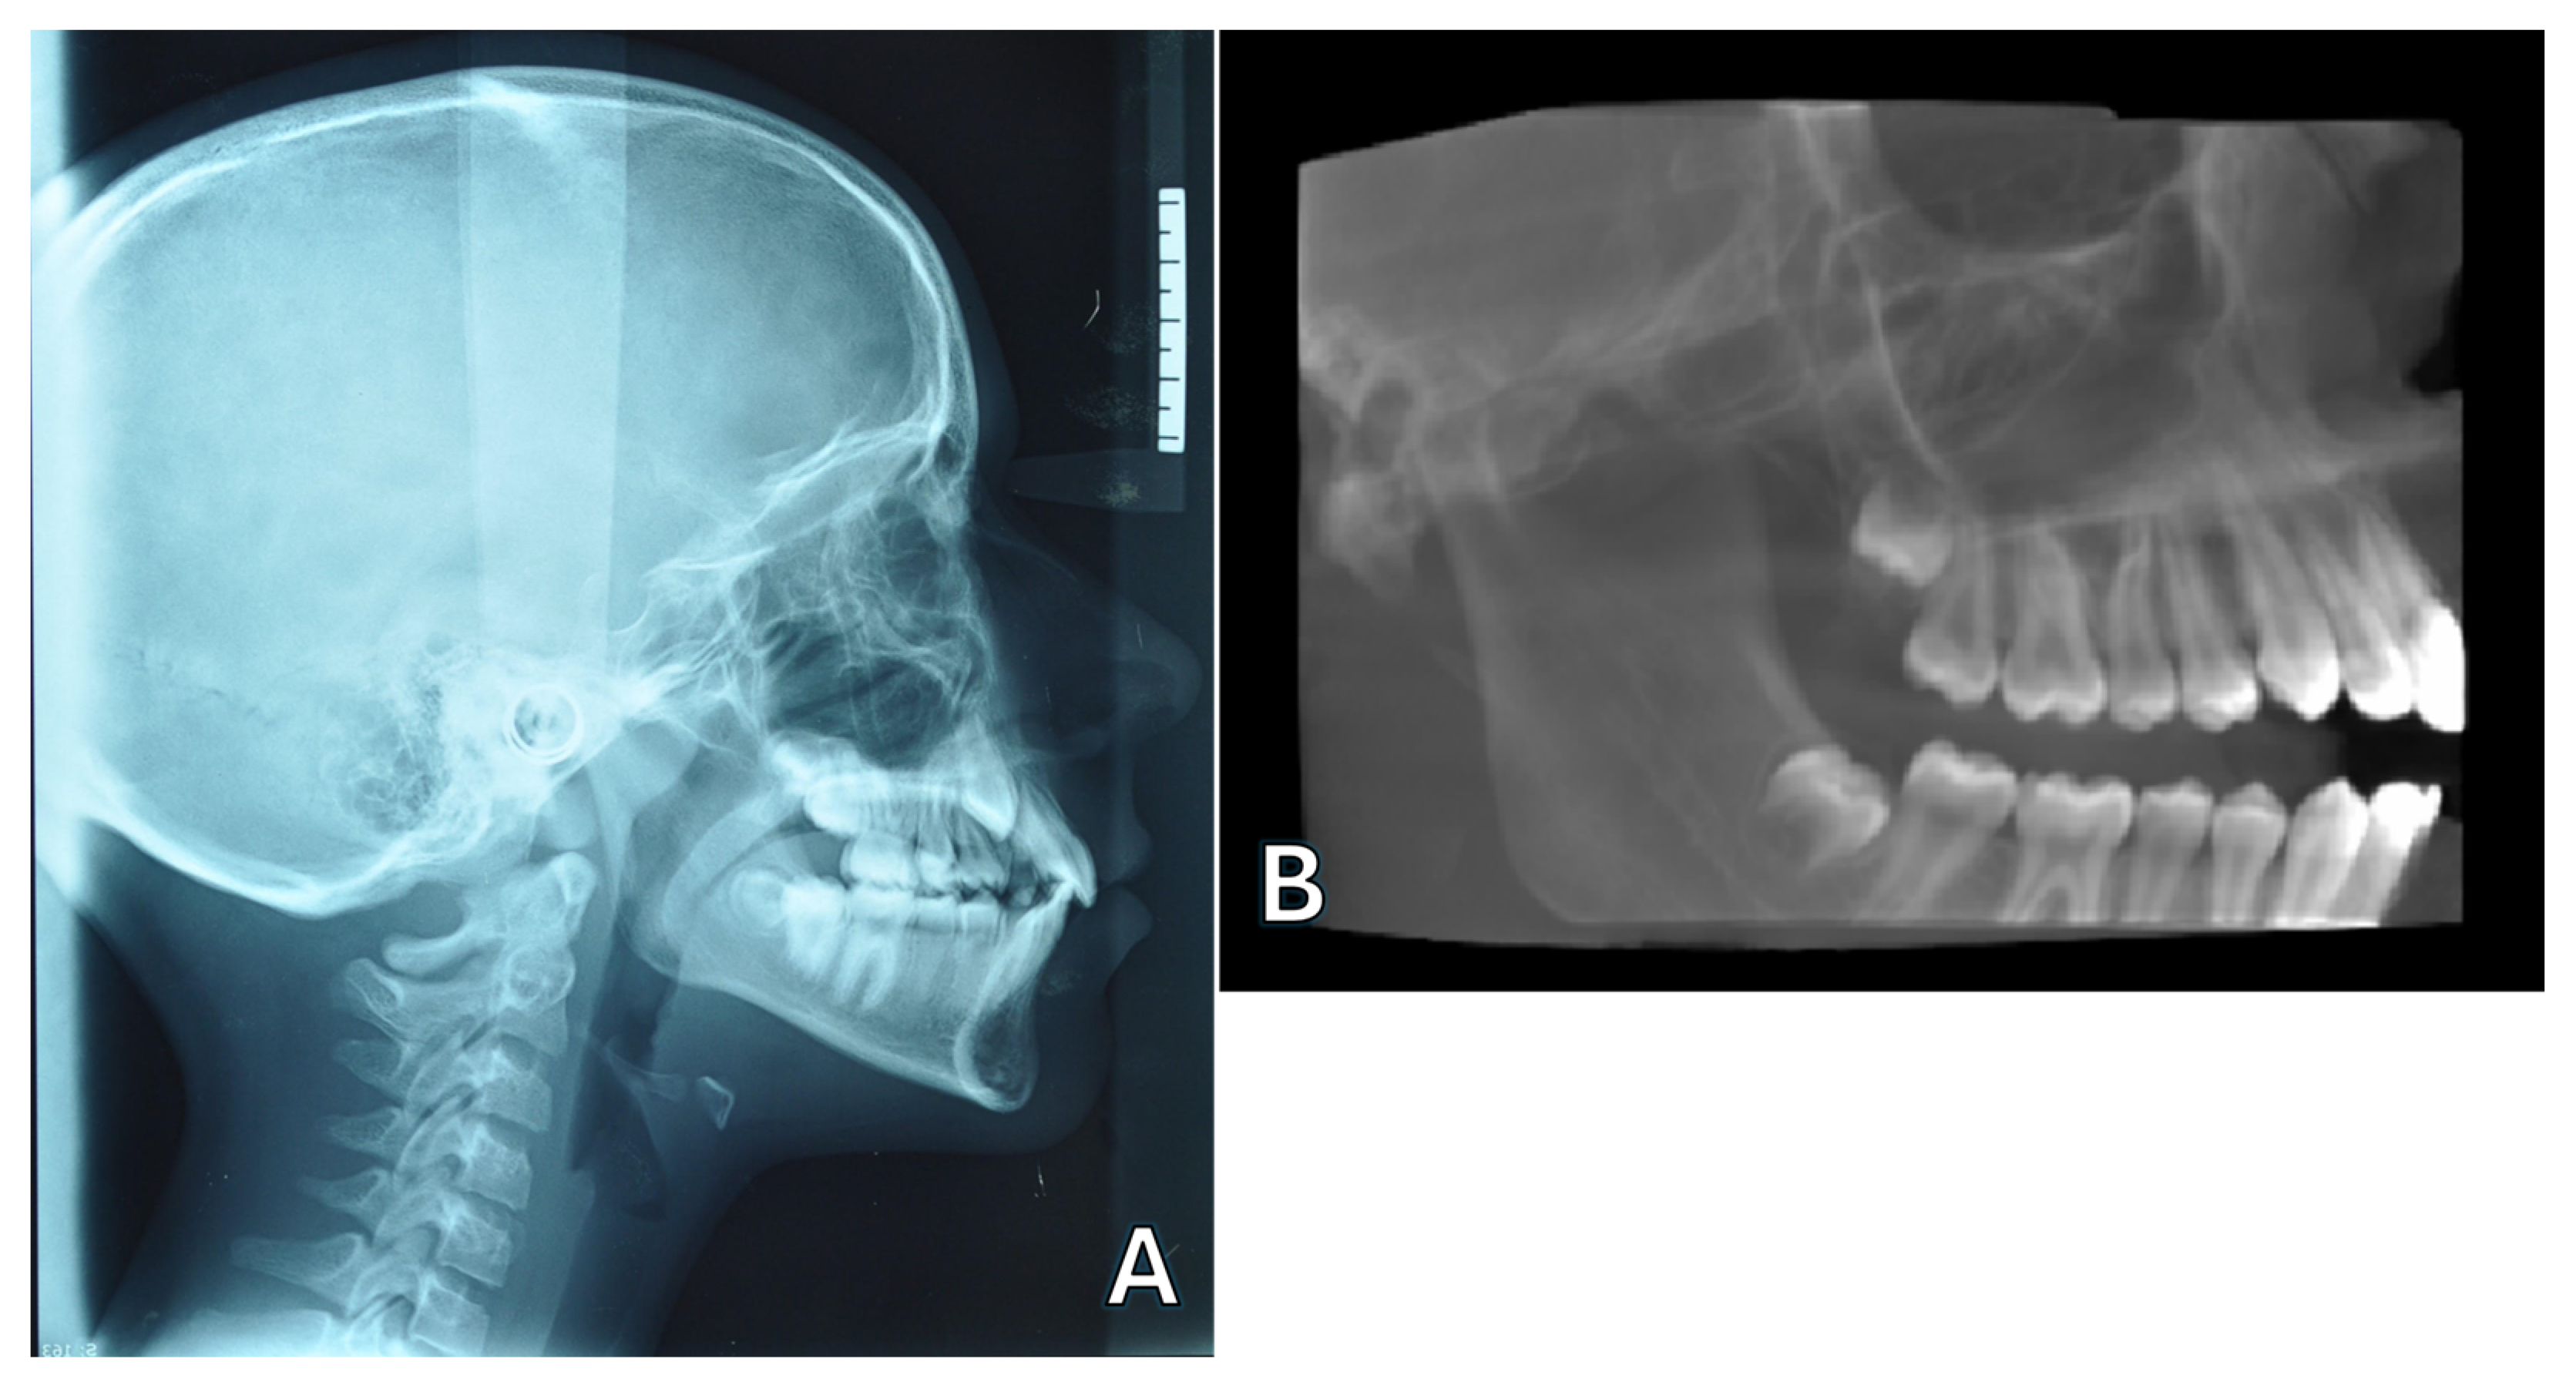

3.2. CBCT for Cephalometric Analysis

4.1. CBCT and Conventional 2D Radiography for Cephalometric Analysis